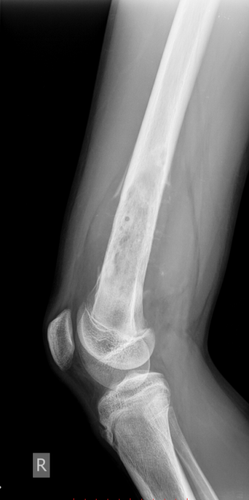

Рентген диагностика заболеваний опорно-двигательного аппарата

Рентгенография костей